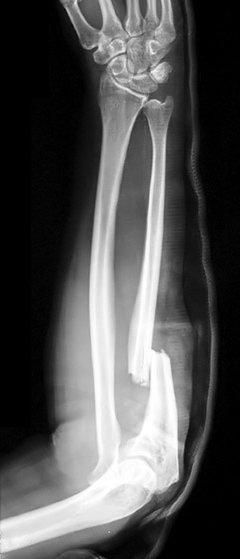

Fractures de Monteggia

Définition: il s'agit de fractures du tiers proximal (généralement) du cubitus avec luxation associée de la tête radiale. Classées en :

Type I - fracture avec luxation antérieure de la tête radiale. C'est le plus fréquent (60 %).12

Type II - fracture du cubitus proximal avec luxation postérieure ou postéro-latérale de la tête radiale (15 %).12

Type III - fracture de la métaphyse cubitale avec luxation latérale ou antérolatérale de la tête radiale (20 %).12

Type IV - fracture du radius et du cubitus à leur tiers proximal avec luxation antérieure de la tête radiale (5 %).12

Mécanisme de la lésion: généralement causée par une chute sur un coude tendu, en extension et en pronation, ou par un coup direct.

Présentation: douleur aiguë, sévère et gonflement de l'avant-bras et du coude. Le nerf interosseux postérieur peut être endommagé.

Fracture de Monteggia

© Jane Agnes (own work), via Wikimedia Commons

Par Jane Agnes (travail personnel), via Wikimedia CommonsInvestigation: Radiographie du radius et du cubitus sur toute leur longueur, y compris le poignet et le coude - les clichés AP et latéraux sont généralement suffisants, mais il peut être nécessaire d'effectuer des clichés radiocapitellaires.

Prise en charge: chez l'adulte, immobiliser l'articulation dans une attelle et l'orienter vers une réduction ouverte et une fixation interne. La plupart des fractures de Monteggia en pédiatrie sont traitées à l'amiable.13

Les fractures isolées du cubitus proximal sont rares. Il faut toujours rechercher une fracture/dislocation de Monteggia.